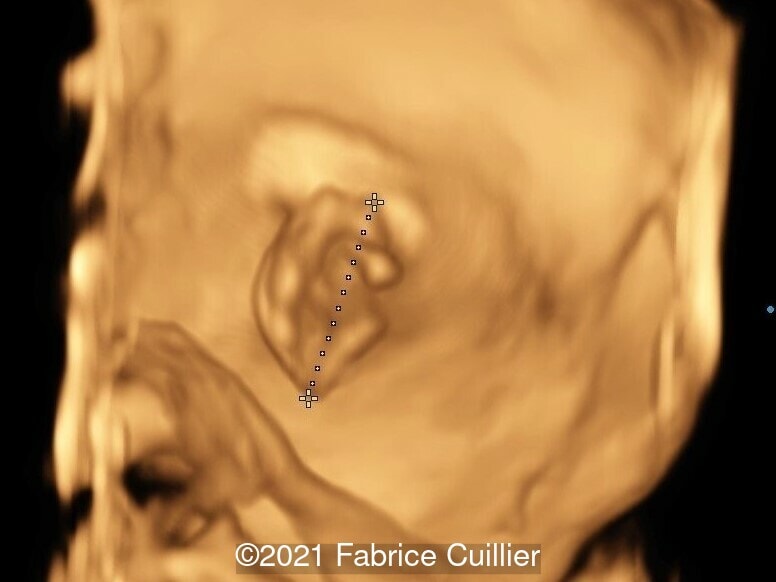

• Images 8,9: Ultrasound at 23 weeks gestation showing an amniotic band near the external right ear causing a stricture on 3D image.